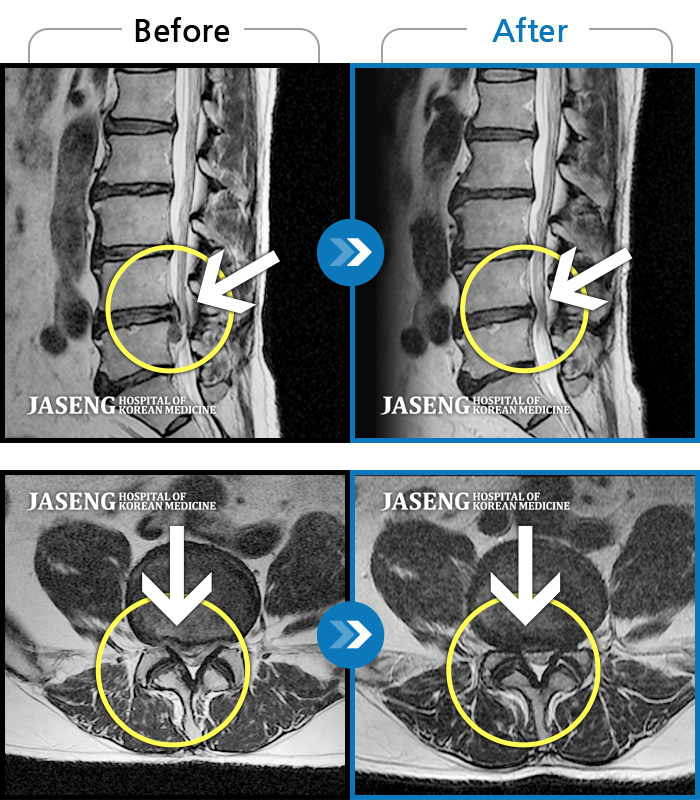

Before

After

환자에게 사전 동의를 받아 동일 조건에서 촬영되었습니다.

개인에 따라 치료 후 부작용이 발생할 수 있으니 의료진과 상담 후 치료를 진행하시기 바랍니다.

요부 및 좌하지 통증으로 기상 후 통증

요부 및 우하지 통증